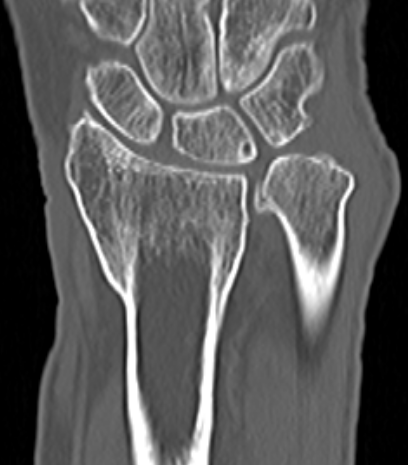

CT

CT guided 3D planning

- RCT of 40 patients with radial malunion

- 2D versus 3D planning and patient specific surgical guides

- 3 degree better correction in 3D group

- non significant trend towards better outcomes in 3D group

Intra-articular osteotomy

Indication

Step deformity

No radiocarpal osteoarthritis

Technique

Dorsal 3/4 approach and open radiocarpal joint